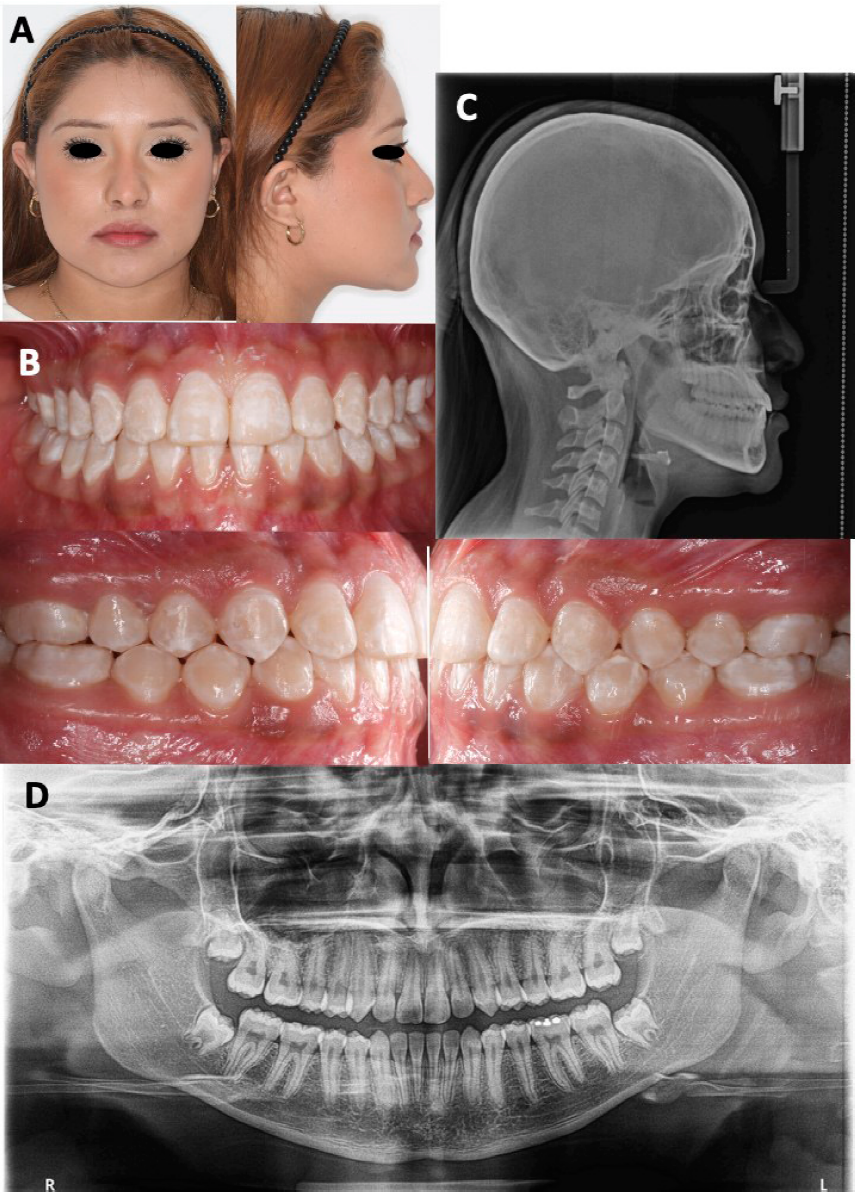

Al final del tratamiento, se mantuvo el perfil recto y mejoró la sonrisa (Figura 4. A), la corrección de la mordida cruzada anterior, Clase I molar y canina (Figura 4. B). Se obtuvo buen paralelismo radicular (Figura 4. C), proinclinación de incisivos maxilares y retroinclinación de incisivos mandibulares (Figura 4. D) (Tabla 1). En la superimposición, se observó la rotación de la mandíbula en sentido de las manecillas del reloj y la proyección del mentón hacia abajo, el cambio en la posición de los molares y los incisivos para lograr la compensación y acompañado de un cambio en la posición de los labios mejorando el perfil.

Figura 4 Fotografías y radiografías finales. A. Fotografías faciales finales de frente y lateral. B. Fotografías intraorales finales donde se observa Clase I molar y canina con buen asentamiento oclusal. C. Radiografía lateral de cráneo final: proinclinación de incisivos maxilares, retroinclinación de incisivos mandibulares, buena proyección labial. D. Ortopantomografía final con buen paralelismo radicular.